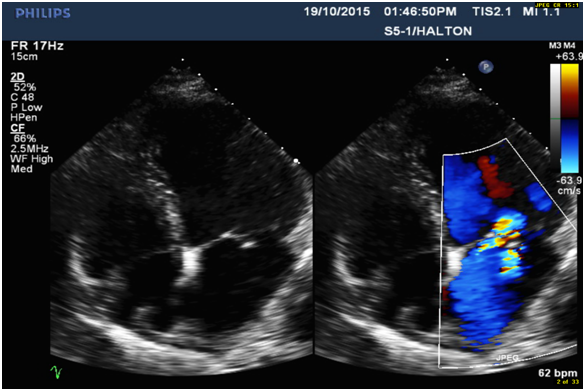

5. Eccentric anteriorly directed severe MR jet area over 50% (Figure 2) with MR ERO 0.47cm2 (Figure 3) and Vena Contracta 0.76cm (Figure 4), which is consistent with posterior flail leaflet of MVP.

Figure 2: Eccentric wall impinging Jet Area over 50% is anteriorly directed, consistent with flail posterior MV leaflet.

Diagnosis of MVP with flail posterior leaflet and grading of MR severity

Physical examination and 2-dimensional (2D) echocardiography are the diagnostic gold standards for MVP [4]. According to echo findings I listed above, together with the patient’s symptoms (SOB and chest discomfort) and pansystolic murmur heard at the apex, the patient was diagnosed as severe MVP with flail posterior leaflet. Echo criteria of flail leaflet includes leaflet tip pointing to LA without systolic coaptation (Figure 1,2,4), torn chordae, double contour (parallel sign) between flail and normal leaflets (Figure 4), and eccentric MR jet direction opposite to the location of the flail leaflet (Figure 2 and 4) [3,4]. Doppler echocardiography is essential in determining the severity of MR. According to ASE guideline, criteria for severe MR includes a vena contracta width ≥ 0.7 cm, large central mitral regurgitation jet (area >40% of left atrium), pulmonary vein reversal, effective regurgitant orifice >40 mm2 and others [3,5]. The echo findings and Doppler measurements strongly support a severe MR in the patient (Table 1).